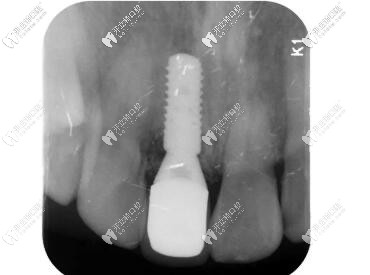

X線顯示:臨時(shí)修復(fù)體就位良好;

門牙外傷過渡義齒修復(fù)

X線片顯示就位良好;

瑞士iti親水BL種植體種植后x片